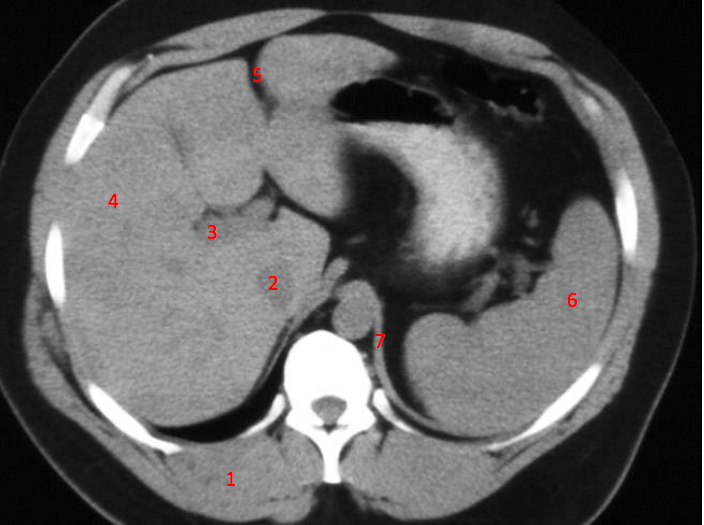

1

Number 3?

IVC

2

Number 1?

R Kidney

3

A

4

Perfectly

Q

Number 2?

How well did you know this?

Not at all

5